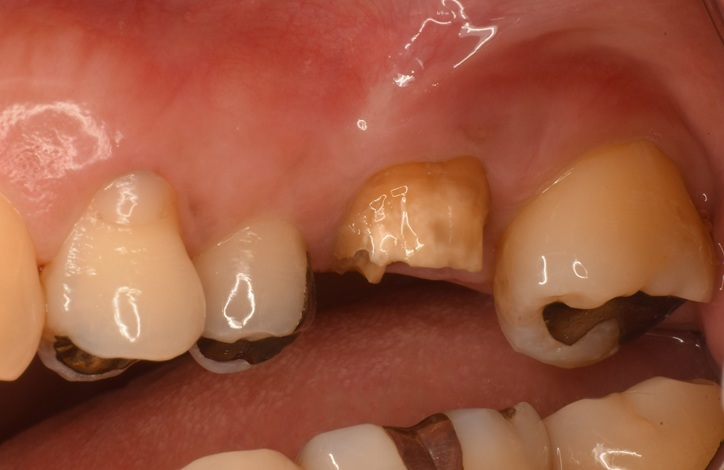

Case5

| 治療名 | サイナスリフトを併用したインプラントブリッジ症例 |

| 治療説明 |

奥歯に入っていたブリッジの支台歯にむし歯が見つかり、やむを得ず抜歯となりました。結果として奥歯が3本分欠損したため、患者さんとの相談のうえ、インプラントによる治療を選択しました。 |

| 治療回数・期間 | 約9ヶ月 |

| 副作用とリスク | ・入れ歯や従来のブリッジと比べ、治療期間が長くなる場合があります。 ・骨造成(GBRやサイナスリフト)を伴う場合、さらに治療期間が延びることがあります。 ・インプラント手術後には、一時的に違和感、痛み、腫れ、出血が生じることがありますが、通常は2日〜1週間で落ち着きます。 ・サイナスリフトは、まれに上顎洞への感染リスクがあるため、術後の経過観察が重要です。 |

| 料金(税込) | 小規模GBR:110,000円 サイナスリフト:220,000円 インプラント一次手術×2本:440,000円 二次手術×2本:110,000円 上部構造〈インプラントブリッジ〉:495,000円 合計:1,375,000円 |